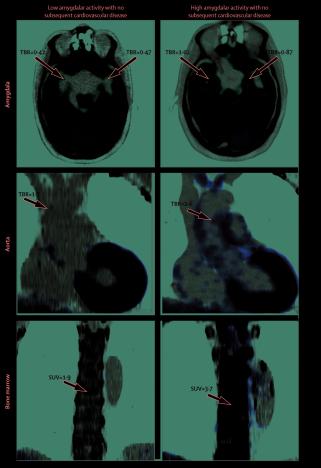

Scans a brain, bone and artery used in a study carried out by Massachusetts General Hospital and Harvard Medical School which associates the brain region called the amygdala, an area linked to stress, to greater risk of heart disease and stroke are seen in an undated image released January 11, 2017 by The Lancet which published the research (Photo: The Lancet Handout via REUTERS)

Scans a brain, bone and artery used in a study carried out by Massachusetts General Hospital and Harvard Medical School which associates the brain region called the amygdala, an area linked to stress, to greater risk of heart disease and stroke are seen in an undated image released January 11, 2017 by The Lancet which published the research (Photo: The Lancet Handout via REUTERS) LONDON – People with heightened activity in the amygdala, an area of the brain linked to stress, may be at greater risk of heart disease and stroke, scientists said on Thursday in research that could lead to new ways to treat stress-related heart problems.

Publishing their work in The Lancet medical journal, the researchers said the stress signalled in the amygdala is also linked to increased bone marrow activity and to inflammation in the arteries, which can cause heart attack and stroke.

Exploring the links, the scientists said a plausible biological mechanism could be that the amygdala triggers the bone marrow to produce extra white blood cells, which then cause the arteries to develop plaques and become inflamed.

In this research, scientists gave 293 patients brain and body scans to record their brain, bone marrow and spleen activity and inflammation of their arteries.

The researchers found that those with higher amygdala activity were more likely to have subsequent cardiovascular disease, and more likely to develop problems sooner than those with lower activity.